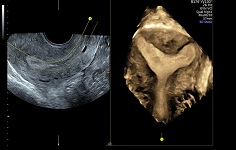

Клинические изображения VOLUSON S10: